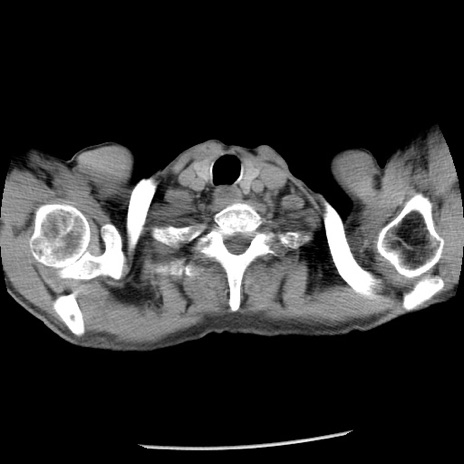

症例26(横断像)

【症例】80歳代男性

【主訴】嘔吐

【現病歴】昨晩2回嘔吐あり、今朝になっても嘔吐あり。来院。

【既往歴】胃潰瘍

【身体所見】意識清明、BT 37.6℃、BP 166/95mmHg、HR 100bpm、SpO2 97%、腹部:平坦・軟、腸蠕動音聴取良好、圧痛なし。

【データ】WBC 21900、CRP 1.46